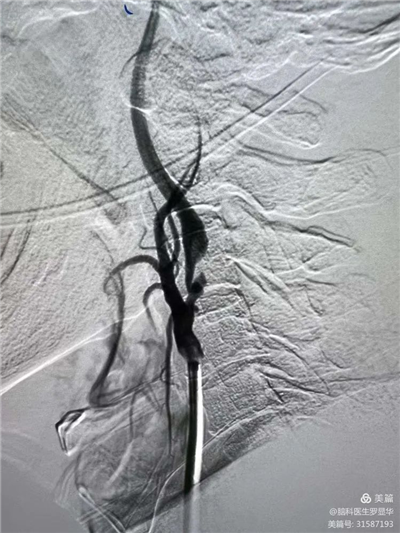

手術(shù)過(guò)程:指引導(dǎo)管到位Xbg安康新聞網(wǎng)

手術(shù)過(guò)程:球囊擴(kuò)張后,protege支架到位Xbg安康新聞網(wǎng)